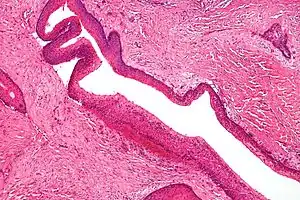

Micrograph showing keratocystic odontogenic tumour, a common finding in nevoid basal-cell carcinoma syndrome (H&E stain)

2. Odontogenic keratocyst: Seen in 75% of patients and is the most common finding. There are usually multiple lesions found in the mandible. They occur at a young age (19 yrs average).